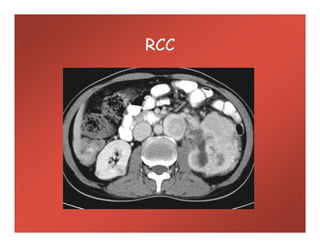

RCC